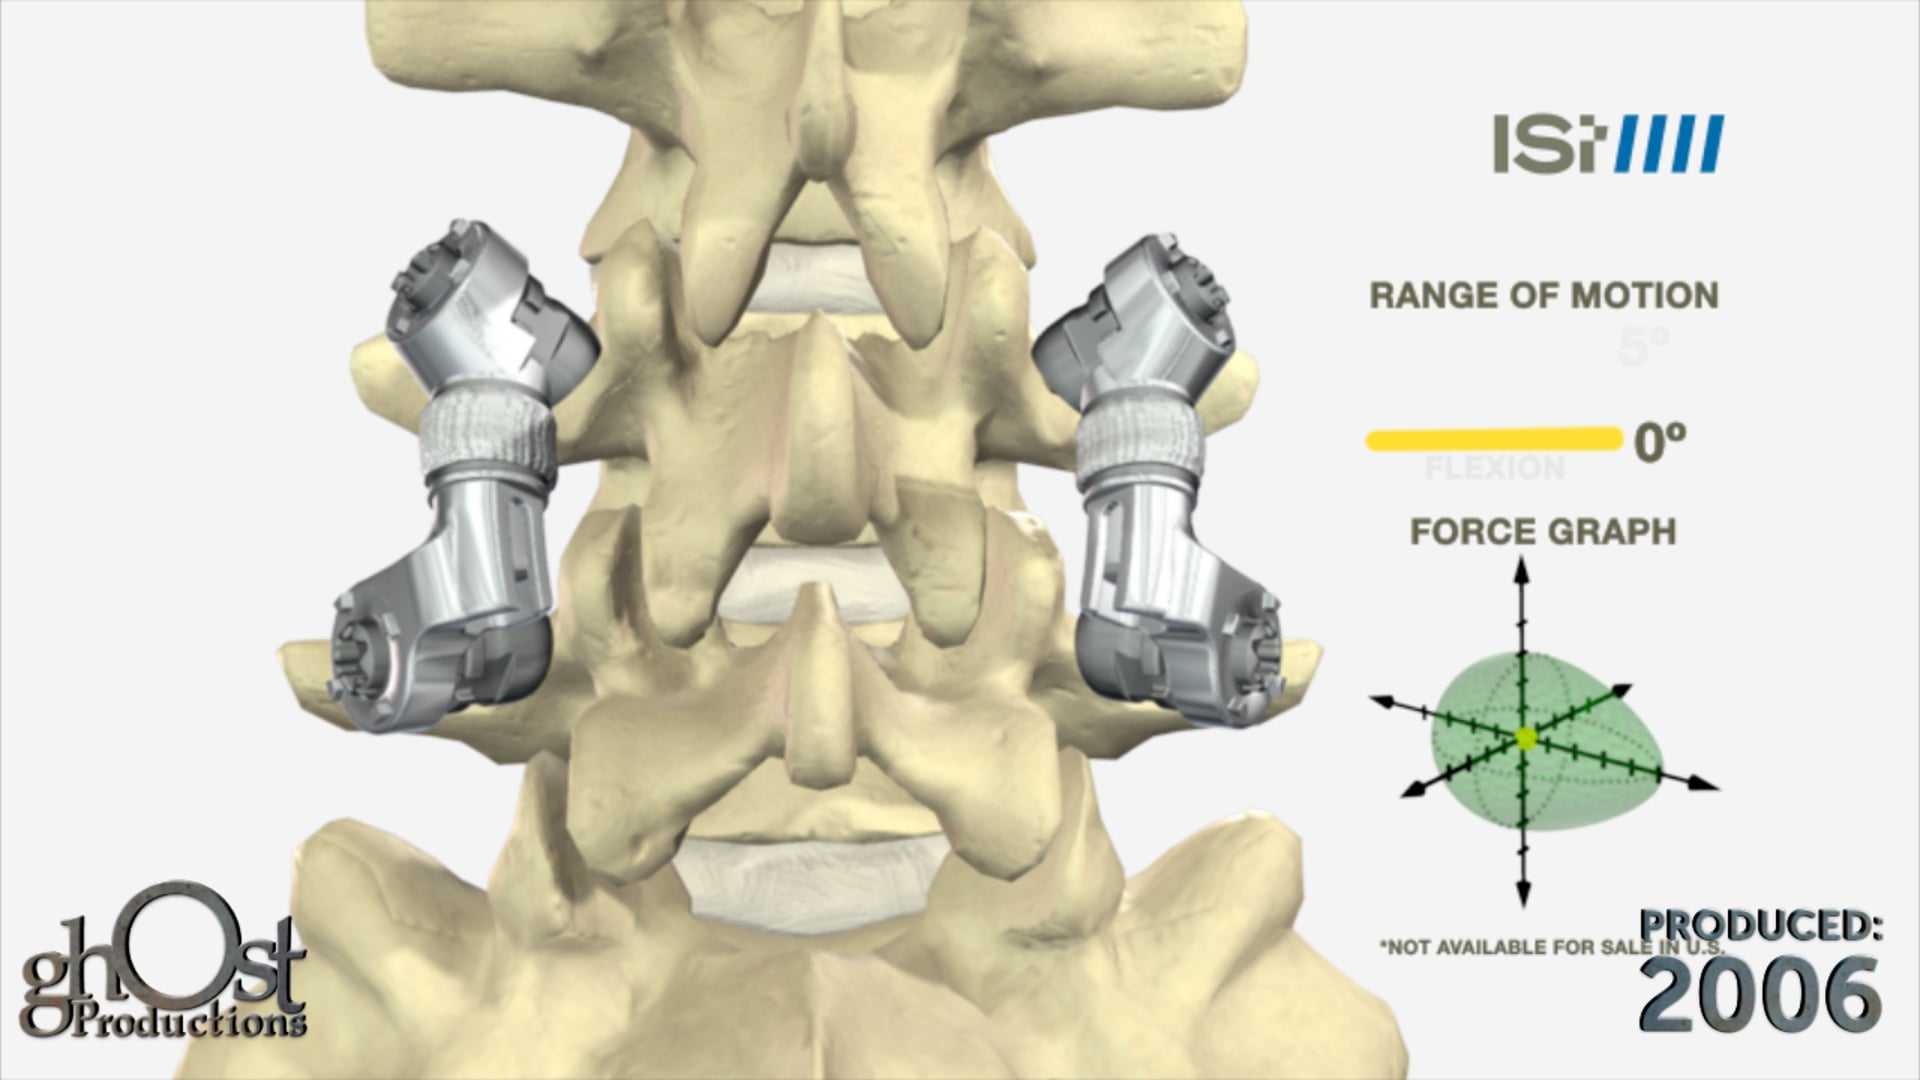

Ghost Productions provided Innovative Spinal Technology with an animation of its Paramount MicroMotion device. The Paramount MicroMotion is a spinal fusion device that uses new technology that allows for preserved motion. As seen in the biomechanics chart in the animation, the device provides a better range of motion as compared to traditional fusion.

Innovative Spinal Technology has partnered with Ghost Productions to create an animation showcasing their latest product, the Paramount MicroMotion device. This innovative spinal fusion device utilizes cutting-edge technology to preserve motion, providing patients with a better range of motion than traditional fusion methods. The animation features a biomechanics chart that clearly demonstrates the device's superior performance. This video is a must-see for anyone interested in the latest advancements in spinal fusion technology.